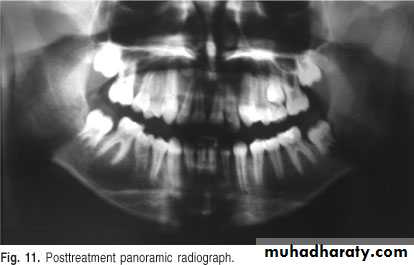

A 11-year-old female with swelling on the right side.

impacted canine